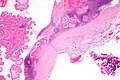

| LM | papillae with a two rows of pink (eosinophilic) epithelial cells (with cuboidal basal cells and columnar luminal cells), fibrous capsule, cystic space filled with debris, lymphoid stroma |

- Papillae (nipple-shaped structures) with a two rows of pink (eosinophilic) epithelial cells (with cuboidal basal cells and columnar luminal cells) - key feature.

- Fibrous capsule - pink & homogenous on H&E stain.

- Cystic space filled with debris in situ (not necrosis).

- Lymphoid stroma.